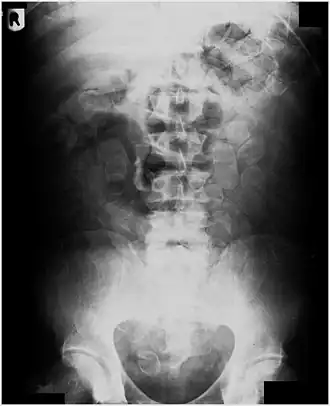

Abdominal X-ray showing small packages of cocaine swallowed by a trafficker. -